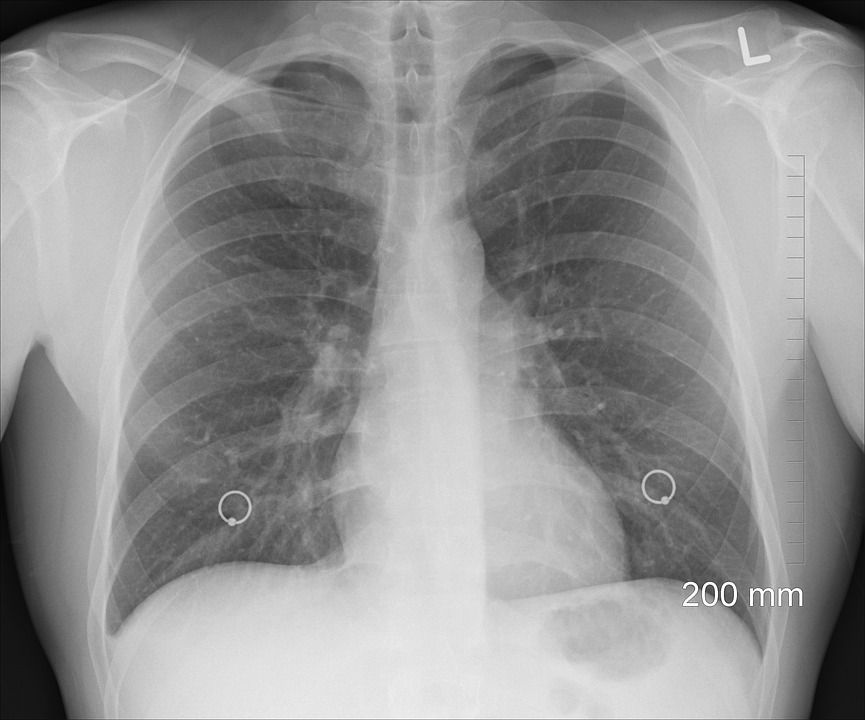

Tuberkulóza, která tiše spí v těle, nehlásí se kašlem, pocením ani únavou, není vidět na rentgenu.

„Zajímá nás, co číhá pod hladinou. Latentní tuberkulózní infekce v Česku ohrožuje několik desítek tisíc pacientů před nebo po transplantacích a těch, co čekají nebo procházejí biologickou léčbou nemocí, jako například Crohnova choroba, idiopatické střevní záněty, roztroušená skleróza, revmatoidní artritida, psoriáza ale i astma a podobné. Ohrožuje i pacienty na dialýze. Mykobakterie tuberkulózy mohou v klidu „spát“ v jejich těle. Ve chvíli, kdy těmto pacientům léky na jiné onemocnění sníží imunitu, se bacil vzbudí a oni pak nedokáží vzplanutí tuberkulózy čelit. Pacienti, kteří podstoupili transplantaci orgánů, především plic, a mají latentní tuberkulózní infekci, čelí až 70procentnímu riziku vzplanuti nemoci,“ říká prof. MUDr. Martina Vašáková, Ph.D., předsedkyně České pneumologické a ftizeologické společnosti (ČPFS). Latentní tuberkulózní infekce nemá typické projevy, na rentgenu se neukazuje, a přitom pacienta přímo ohrožuje na životě. „Správně by ti, kteří mají podstoupit transplantaci solidního orgánu nebo kostní dřeně, či právě biologickou léčbu, měli být otestováni tuberkulinovým kožním testem a IGRA testem z krve. Jestliže jsou tyto testy – jeden nebo druhý nebo oba naráz - pozitivní, měli by dostat léky. Ne každé pracoviště ale postupuje dle našich doporučení a své pacienty testuje. Nemáme tak přehled o pozitivních nálezech a o tom, zda a jestli vůbec tyto pacienty léčí,“ vysvětluje prof. Vašáková. Na rozdíl od lidí s aktivní tuberkulózou se lidé s latentní tuberkulózní infekcí mohou léčit doma.